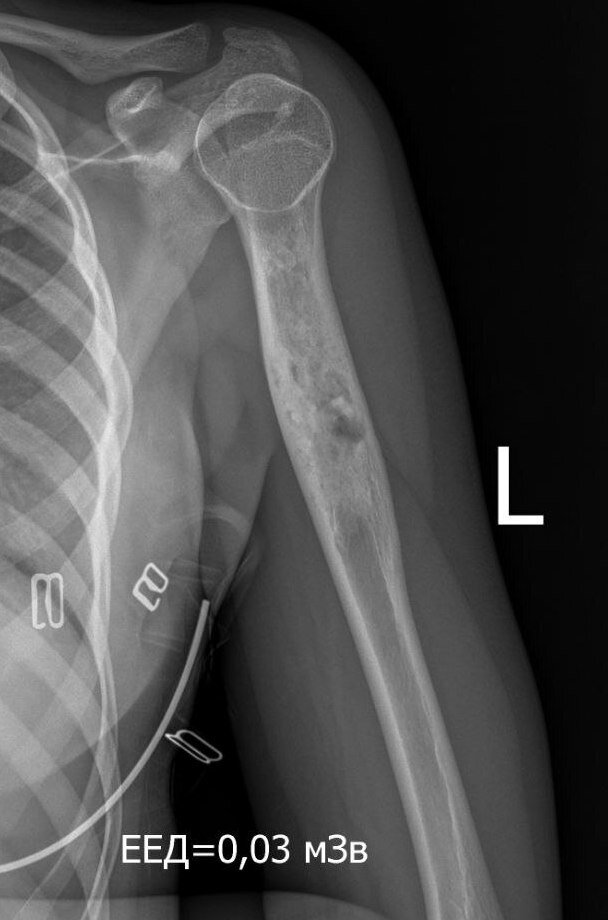

"Sasha's mother called, crying from happiness. They are now in Kyiv, just got out of the children's oncology center - Everything is fine! The oncologist studied everything from the very beginning, took another X-ray - everything is healing! Olexandra will only need to take some medication to facilitate the growth of her bone. What was thought to be a tumor is growing in the bone itself! And if it goes like this, then before the formation of a complete skeleton - by the age of 18 it should grow completely and then there will be no need for an implant! Annual check-ups, X-rays, and MRIs will continue to monitor her progress to ensure her well-being."

This miraculous turn of events has brought immense joy and relief to Olexandra's family. The family lives in Nikopol which is heavily shelled but they don't want to leave their home. Olexandra has been through two operations - one took place right after the incident and the other one was a biopsy of a tumor (21/09/2023) that turned out to be a benign formation. Now, it has become evident that her bone is regenerating naturally, eliminating the necessity for the previously planned surgery and implant.

Please find all the relevant medical documents attached below for your reference. Photos were cropped as they contained a lot of personal information.